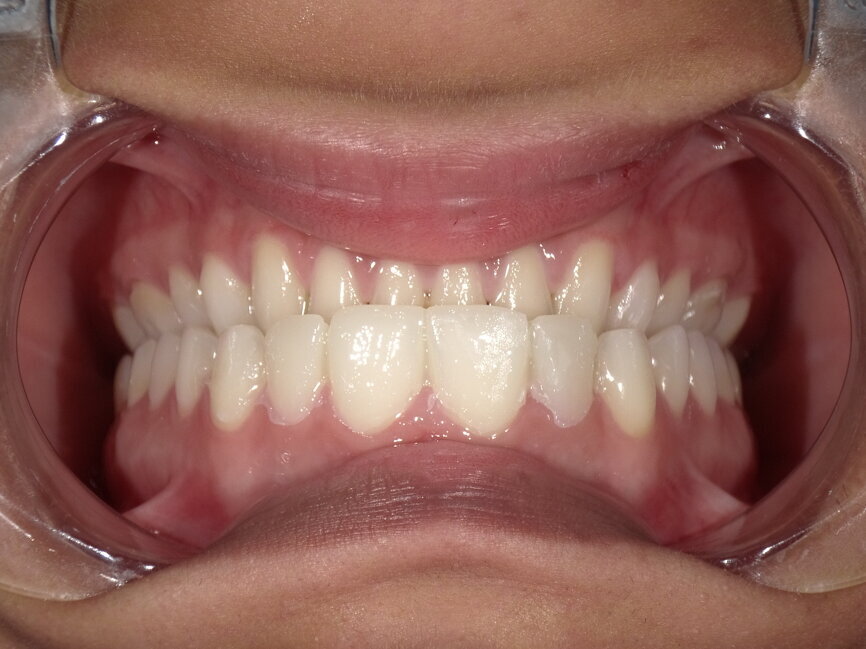

A young female patient visited the clinic requesting for an enhanced smile as she was unhappy with the appearance of her front teeth after completing orthodontic treatment. Upon careful examination it was observed that composite resin restorations were used for diastema closure before orthodontic treatment (Fig 1, 2). The filled teeth had chipped at the incisal edge and had a grey discolouration. After careful evaluation the following treatment options were suggested to the patient:

Fig 2: Pre-operative retracted view

Fig 4: Retracted view after removal of old restorations